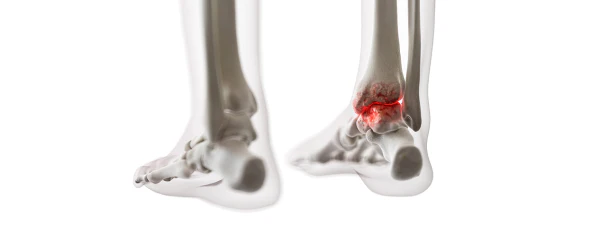

통풍을 적절히 치료하지 않을 경우, 발작성 관절염의 빈도가 증가하고 침범하는 관절 수도 더 많아지며, 회복에 필요한 시간도 증가합니다. 반복적인 관절염은 관절을 점차 손상시키며, 만성적인 관절염으로 진행될 수 있습니다. 또한 통풍성 결절이라 불리는 덩어리가 관절 주위나 피부 조직에 나타날 수 있습니다. 이러한 결절은 요산 결정체의 덩어리로 어느 부분에서든 형성될 수 있으며, 주로 팔꿈치, 귀, 손가락, 발가락, 발목 등에서 발생할 수 있습니다. 때로는 요로 결석을 형성하기도 합니다.

1) 한 군데 관절(엄지발가락, 발목, 무릎 등)이 갑자기 붓고 빨갛게 변하며, 손을 움켜쥘 수 없을 정도로 심한 통증이 발생합니다.

4) 엄지발가락 관절에 염증이 잘 발생하는 것이 특징이며, 무릎, 발, 발목, 손목, 팔꿈치 등 다른 관절에서도 발생할 수 있습니다.